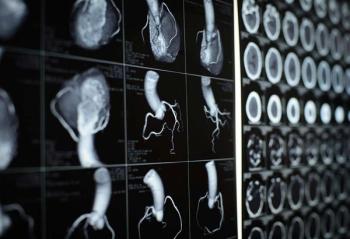

A joint session with the Society for Cardiovascular Computed Tomography (SCCT) took place on the first day of the American Society for Preventive Cardiology 2024 Congress in Salt Lake City, Utah.